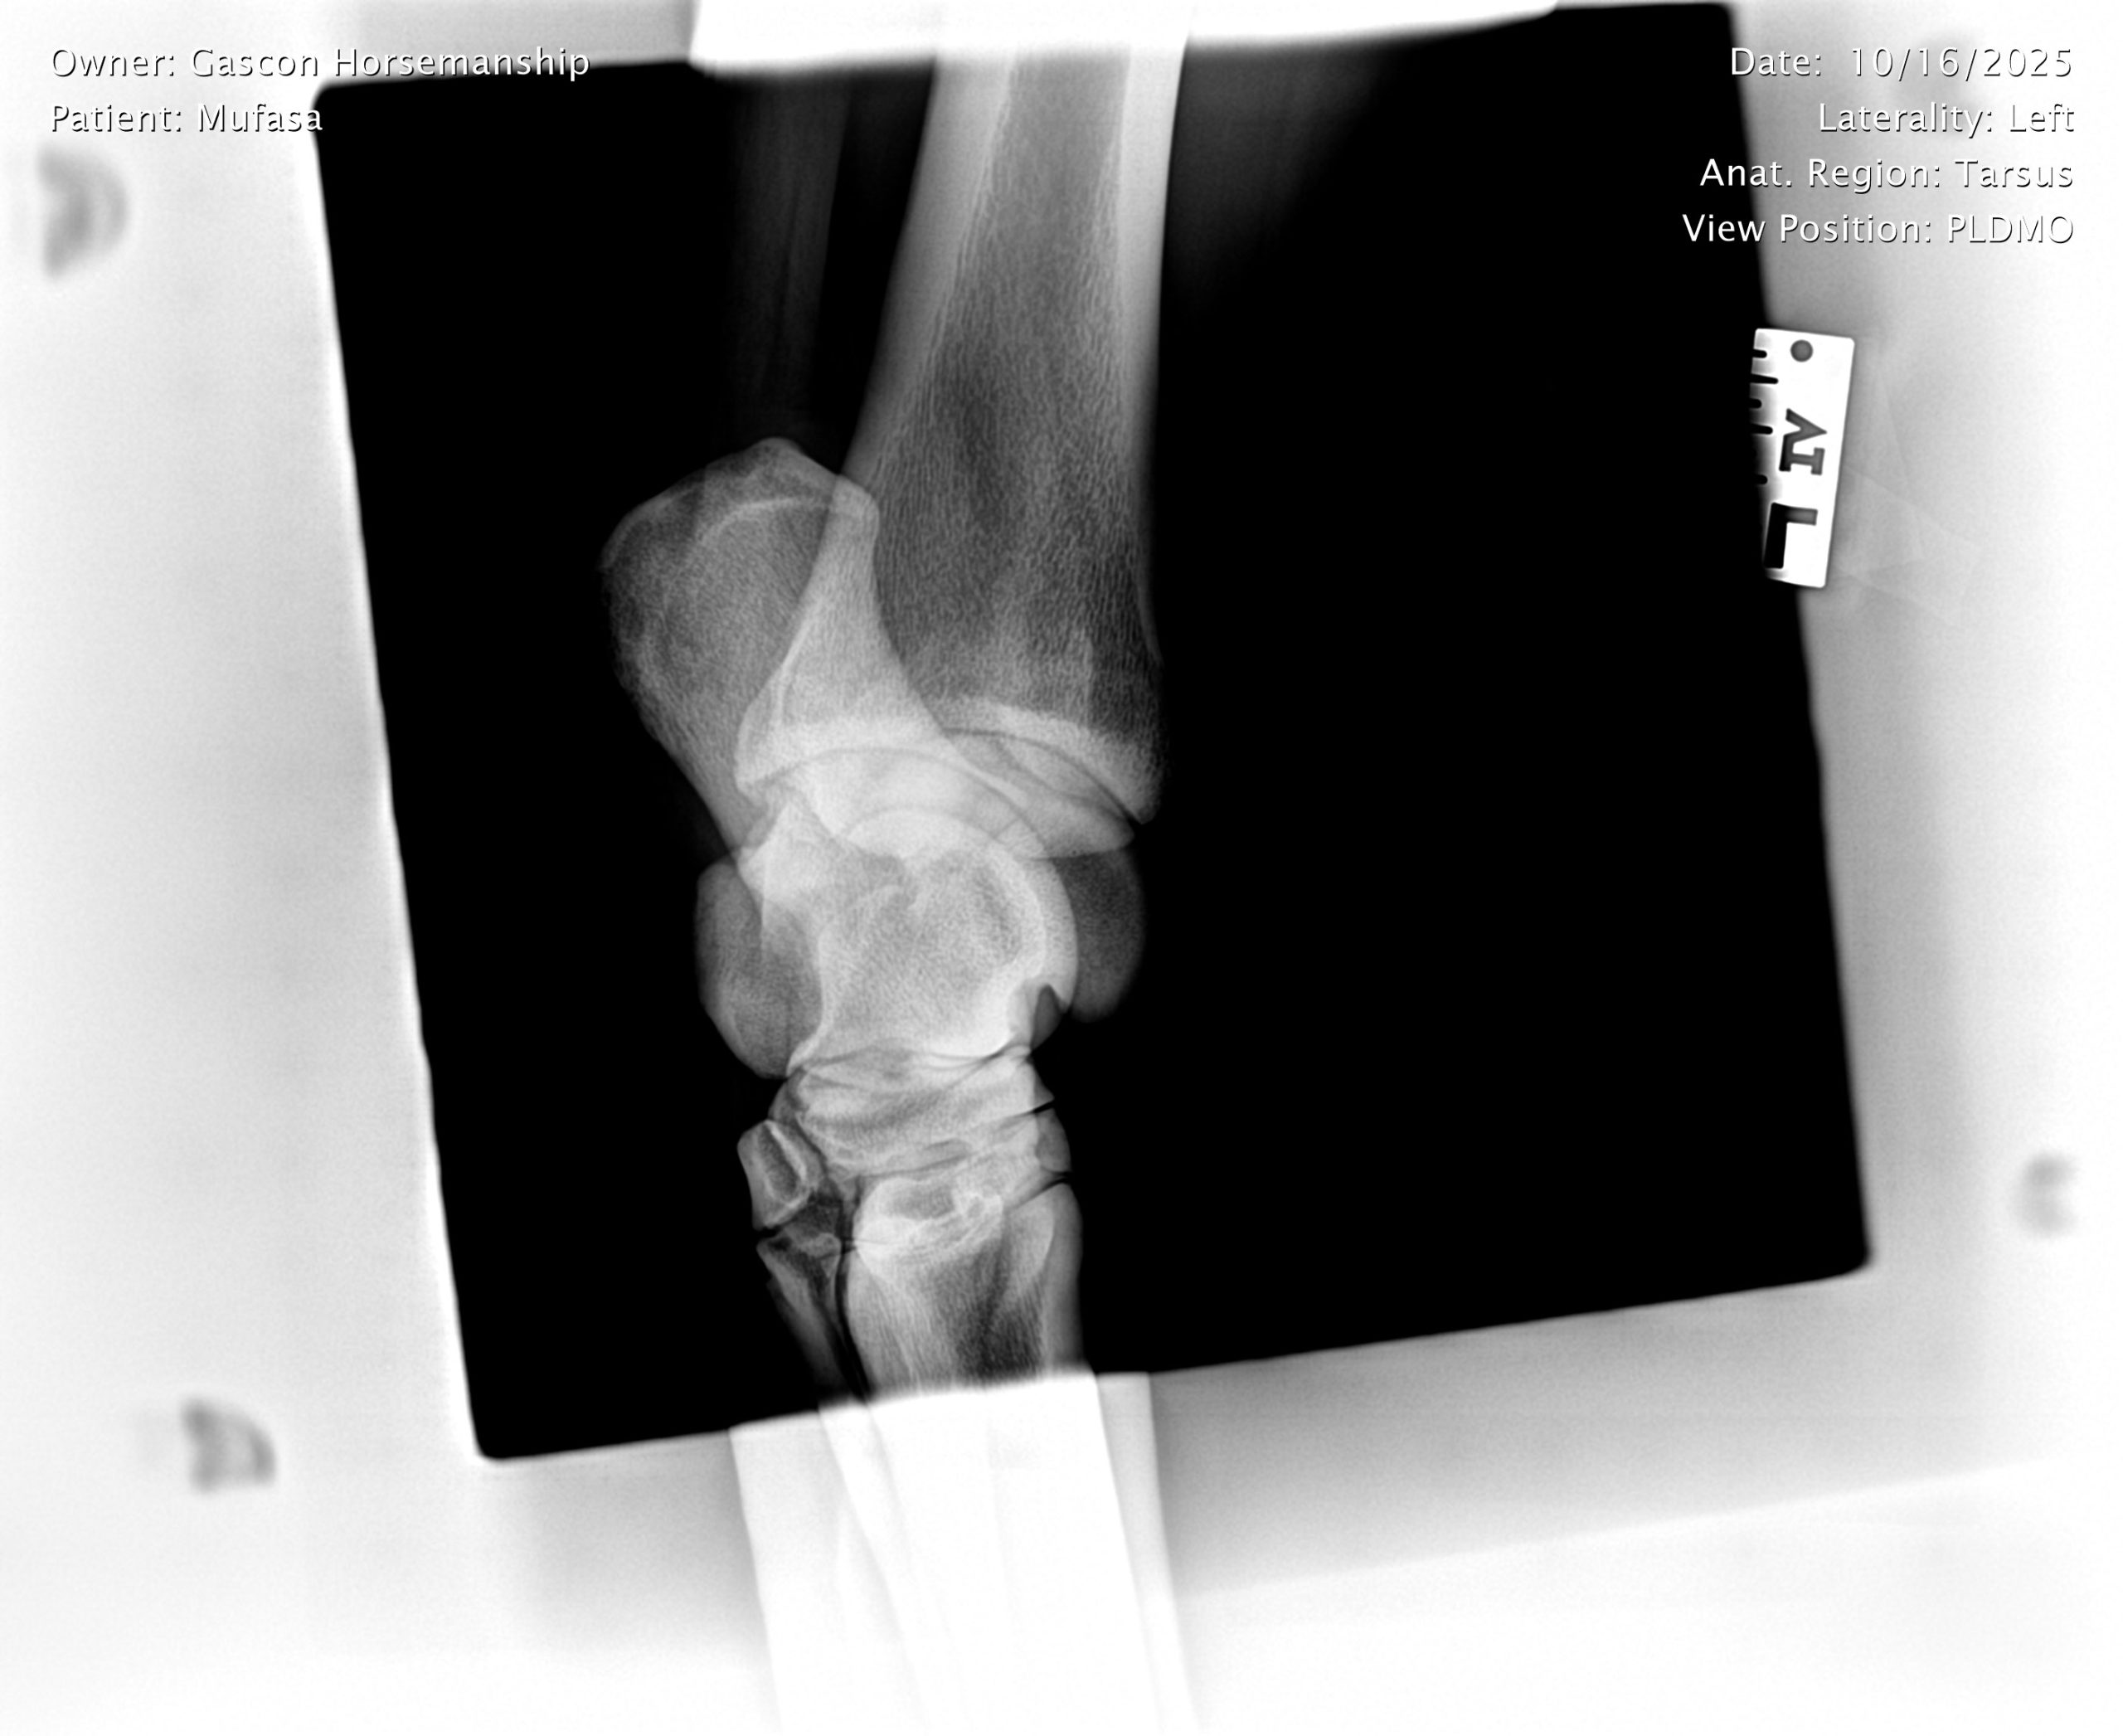

He already has a full pre-purchase exam on file, complete with 25 X-rays included in his album.